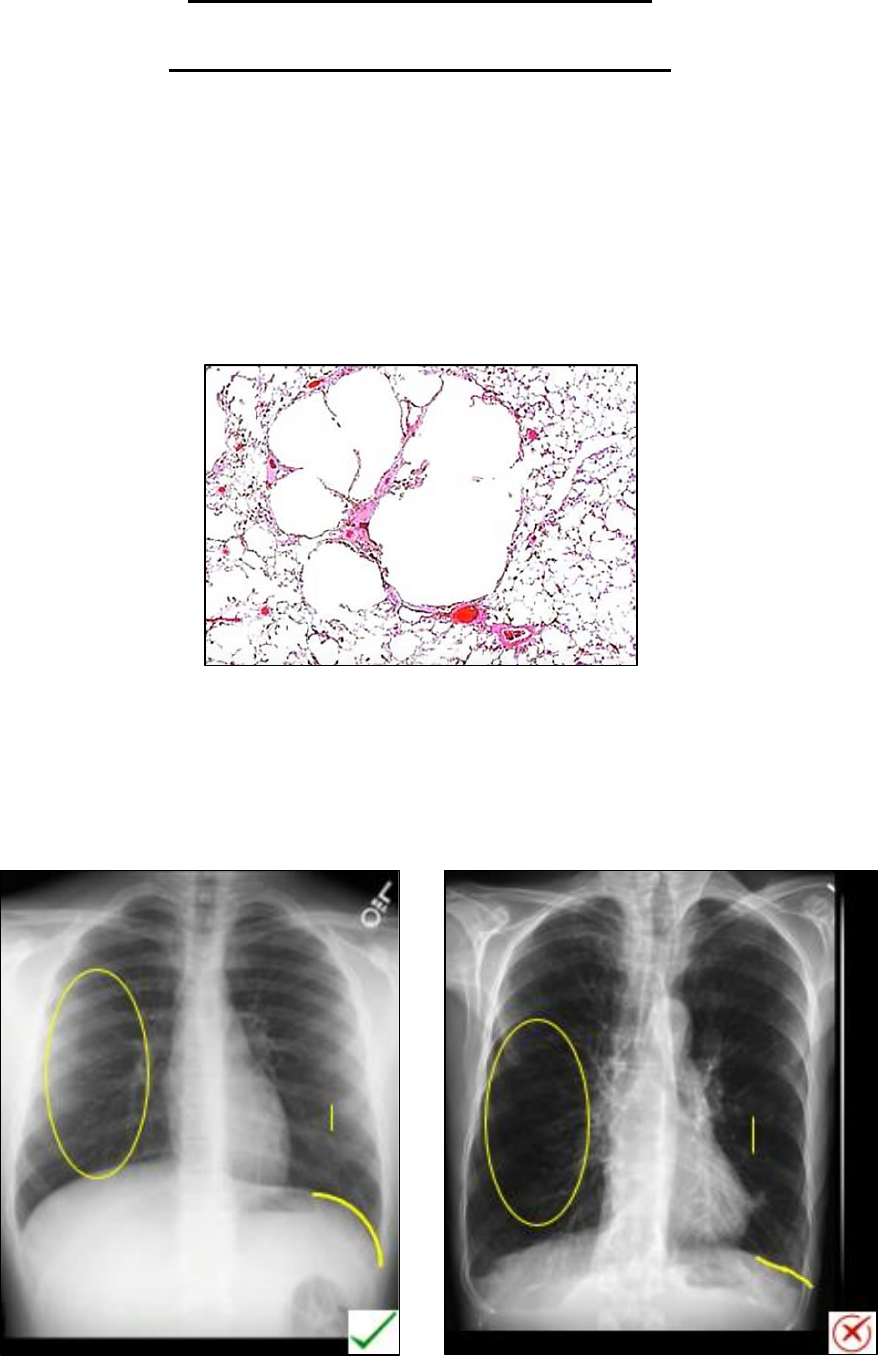

Enfisema Pulmonar

• É o aumento permanente anormal dos espaços aéreos distal aos bronquíolos terminais, acompanhado de

destruição da parede alveolar e sem fibrose óbvia.

• Fatores de risco: Fumo e deficiência de alfa-1-antitripsina

• Sinais ao RX:

- Hemidiafragma achatado: sinal mais confiável

- Aumento da radiolucência dos pulmões

- Costelas amplamente espaçadas

- Espaço aéreo restroesternal aumentado

- Aumento do diâmetro antero-posterior do tórax

• A Tomografia é a modalidade de escolha para detectar enfisema.

• Pela TC é possível discriminar entre enfisema centrolobular, panlobular e paraseptal.

• Centrolobular: localizados centralmente dentro do lóbulo pulmonar secundário, muitas vezes com um ponto

central ou periférico que representa o feixe broncovascular central. Está predominantemente localizado nas

zonas superiores.

• Paraseptal: localizado adjacente às linhas de pleura e septal com distribuição periférica dentro do lóbulo

pulmonar secundário. Os lóbulos afetados são quase sempre subpleurais.

• Panlobular: predominantemente localizado nos lóbulos inferiores, tem distribuição uniforme em partes

do lóbulo pulmonar secundário.